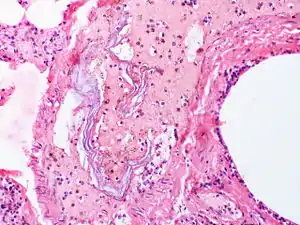

AFE is diagnosed when all other causes have been excluded. The presence of fetal squamous cells or other fetal tissues, including meconium, have been found in the maternal circulation after the event. Diagnosis is also based upon the signs and symptoms observed during the birth or procedures.[2]